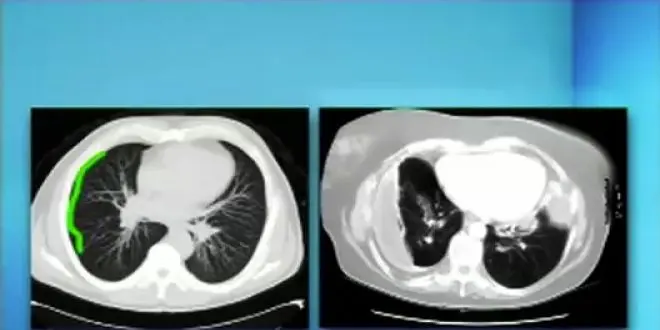

Lex examens complémentaires comportent la radiographie, l'échographie, éventuellement un scanner. La ponction permettra de recueillir le liquide et de l'analyser pour trouver l'origine de la pleurésie.

On parle de pleurésie lorsque la quantité de liquide entre les deux feuillets augmente. Egalement appelée épanchement pleural, la pleurésie peut entraîner les symptômes suivants, une toux sèche, un point de côté, des douleurs au niveau du thorax souvent très vives, ainsi qu'une véritable gêne respiratoire.